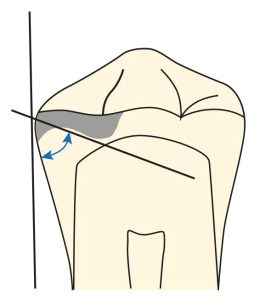

On the abutment teeth adjacent to the tooth-supported denture base, a slightly curved guide plane is shaped by directing the bur from the buccal corner to the lingual corner of the aproximal surface (Figures 10-20).

This guide plane surface should form a curvature with an occlusogingival height of 2-4 mm and not a flat surface when viewed occlusally (Figures 10-21).